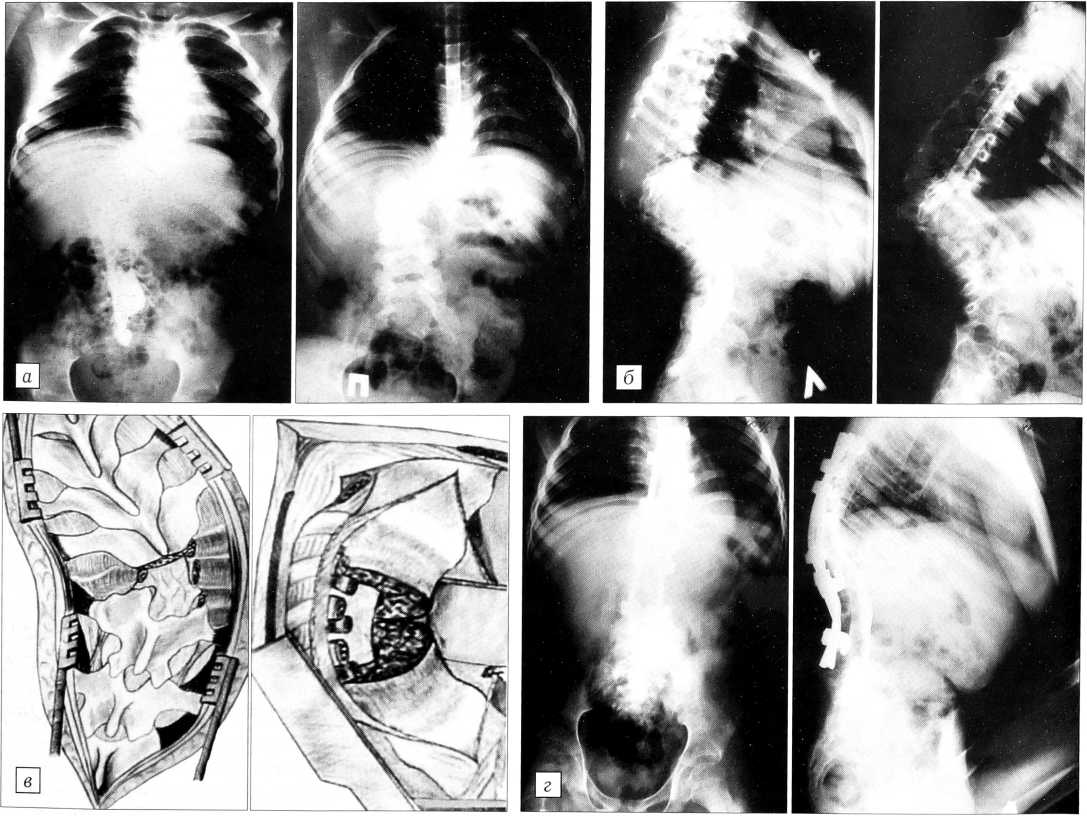

Больная К.,8 лет, страдает врожденным правосторонним грудопоясничным кифосколиозом. Из анамнеза известно, что за год до поступления девочка перестала ходить, развился нижний спастический парапарез, появилось недержание мочи. При осмотре выявляется нарушение всех видов чувствительности с уровня Т11-12, брюшные рефлексы отсутствуют, имеется нижний спастический парапарез с выраженным повышением мышечного тонуса, сухожильной гиперрефлексией на ногах, стопными патологическими знаками, клонусами стоп, защитными рефлексами. На восходящей и нисходящей миелограммах — «стоп-контраст» на вершине деформации (рис. 3, а, б).

Больной произведена операция: расширенная ламинэктомия T11-L2 позвонков,костотрансверзэктомия ТЦ-12 справа, экстирпация двух полупозвонков на вершине искривления, вертебротомия, резекция заднего края тела Т11 позвонка, коррекция деформации системой CD, задний спондилодез аутотрансплантатами из ребер. Интраоперационно после реконструкции позвоночного канала отмечено полное устранение сдавления спинного мозга. На контрольной миелограмме блока субарахноидального пространства нет (рис. 3, г). В неврологическом статусе через 3 мес существенной положительной динамики не выявлено.

Рис. 3. Больная К. 8 лет. Врожденный правосторонний грудопоясничный кифосколиоз. а - восходящая и нисходящая миелограммы в прямой, б — в боковой проекции до операции: «стоп-контраст» на вершине деформации; в схема операции: тотальная спондилэктомия, реконструкция позвоночного канала, коррекция деформации системой CD; г — восходящие миелограммы после операции: прохождение контрастного вещества.